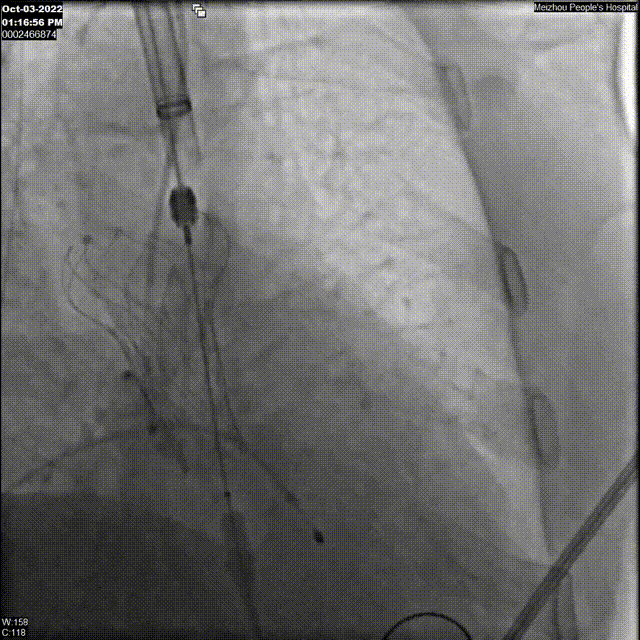

18F球囊后扩影像

瓣膜最终植入结果